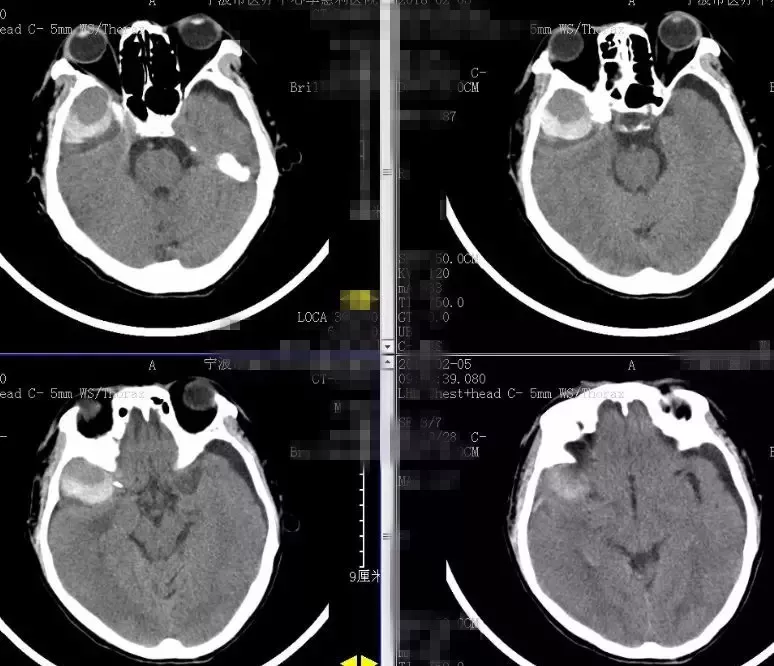

2018-2-13 CTA提示右颞部DAVF可能(图6),建议DSA。仔细阅片CTA未见明显引流静脉,考虑右侧脑膜中动脉假性动脉瘤可能更大。次日行 DSA检查,证实为“右侧脑膜中动脉假性动脉瘤”(图7)。当日即行“右侧翼点入路,脑膜中动脉假性动脉瘤切除加血肿清除术”(图8)。病理回报:镜下纤维细胞增生,可见血凝块伴机化(图9)。2018-2-27 复查CTA提示右侧脑膜中动脉假性动脉瘤术后改变,未见残余及复发(图10)。

图6. 2018-2-13 CTA提示右颞部DAVF可能。

图7. 2018-2-14 DSA提示右侧脑膜中动脉假性动脉瘤。